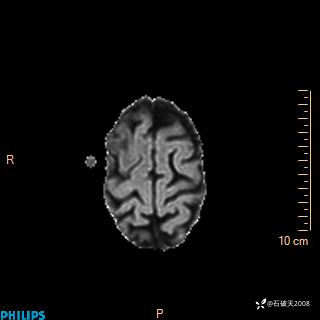

2024.2.21MR

DWI